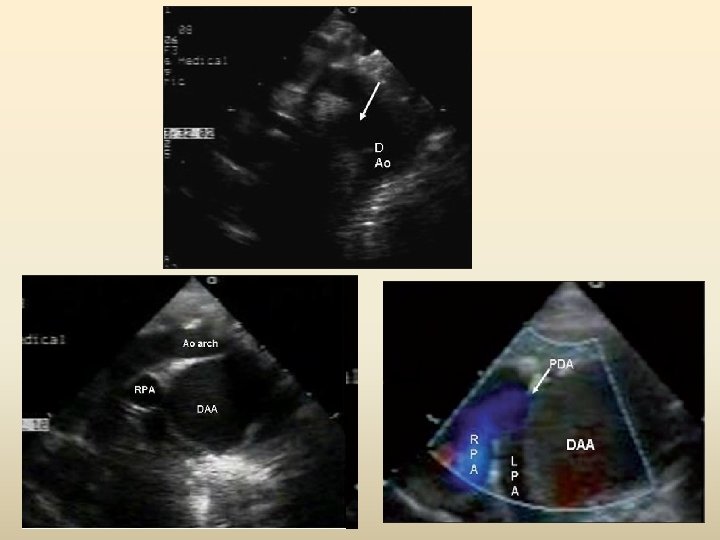

PDA in a Right aortic arch • The PDA is commonly left in origin